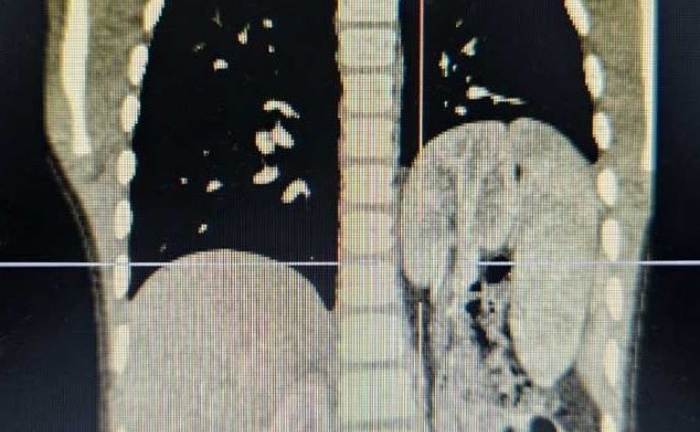

Khối u khổng lồ nặng tới 1,2kg. Ảnh: VietNamNet

VietNamNet dẫn lời bác sĩ chuyên khoa I Hà Anh Tuấn, Khoa Ngoại Thận - Tiết niệu, Bệnh viện Đa khoa tỉnh Tuyên Quang, cho biết bệnh nhân nhập viện trong tình trạng vùng bìu 2 bên có khối u kích thước khoảng 20x20cm, ranh giới rõ, mật độ mềm.

Theo bác sĩ Tuấn, khối u của bệnh nhân bao bọc lấy tinh hoàn, bó mạch tinh và ống dẫn tinh. Sau 1,5 giờ phẫu thuật, kíp mổ đã cắt bỏ khối u và tạo hình da vùng bìu thành công. Trong quá trình phẫu thuật, các bác sĩ phải rất tỉ mỉ để bảo tồn hoàn toàn bộ mạch tinh, ống dẫn tinh và tinh hoàn.